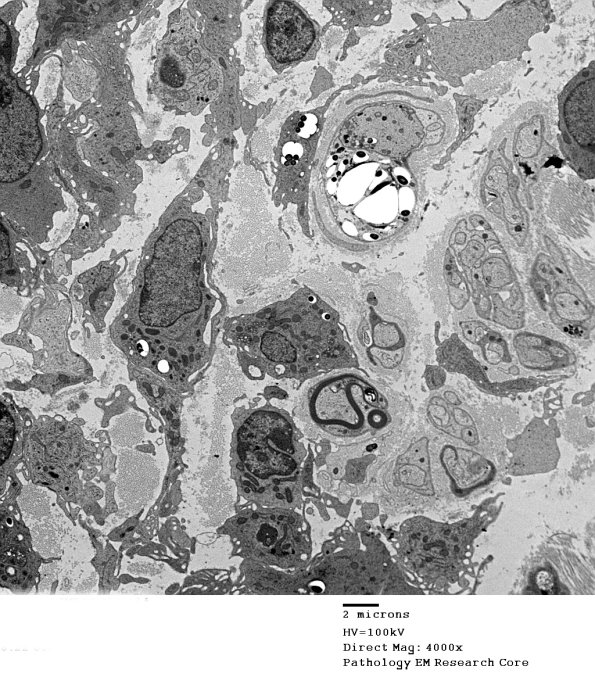

1D5A,B The infected Schwann cell has resulted in a demyelinated axon with an intra-axonal organism. An adjacent macrophage appears to have engulfed bacilli. (electron micrograph)